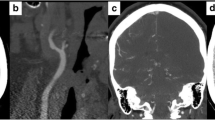

Computed tomography angiography

Multisection CT angiography (CTA) provides high-resolution and high-contrast images of the arterial lumen and vessel wall and is noninvasive. Axial source images provide excellent visualisation of the craniocervical arteries as a consequence of the contrast difference between the enhanced arterial lumen and the surrounding structures. Postprocessing of the source data as MIPs or curved multiplanar reformats MPR produces images that closely resemble those obtained with intraarterial angiography, and voxel-rendering techniques allow a 3D display of the vessels and surrounding soft tissues [78]. CTA of ICA dissections has shown excellent agreement with arterial angiography [79]. A 100% sensitivity and specificity was achieved using the presence of a narrowed eccentric lumen in association with enlargement of the overall vessel diameter as criterion for acute carotid dissection. Other signs of extracranial carotid artery dissection on CT include stenosis, mural thickening, occlusion, aneurysm formation and thin annular contrast enhancement (Fig. 16).

Multisection CTA has also proved useful for diagnosis of VA dissections [80]. Multisection CT achieved 100% sensitivity for detecting stenosis and occlusive and aneurysmal dissections of the VA in 17 patients. There was one misclassification of a severe atherosclerotic lesion as aneurysmal dissection, resulting in a sensitivity of 98%. CTA is also suitable for noninvasive follow-up of patients with extracranial carotid artery or VA dissections. MRI may be better for evaluation of arterial segments near the skull base, as artefacts in this region can hamper CT.